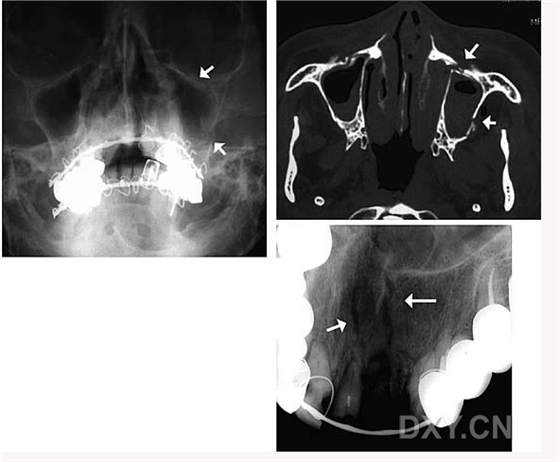

頜骨骨折